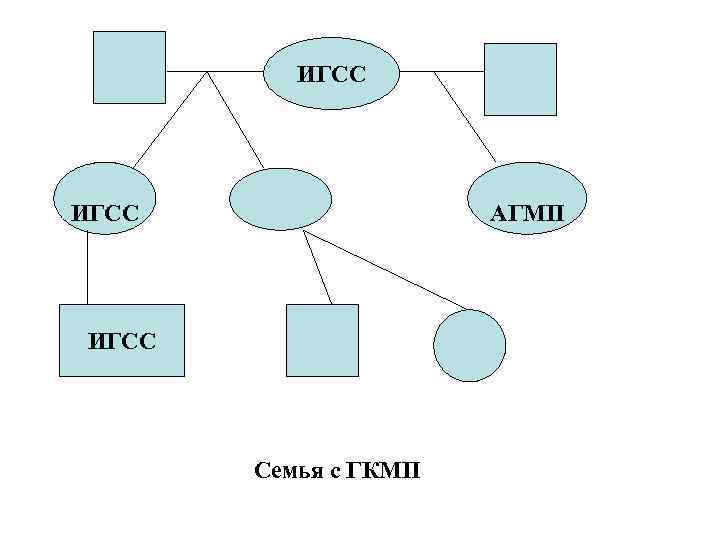

ИГСС АГМП ИГСС Семья с ГКМП

ИГСС АГМП ИГСС Семья с ГКМП